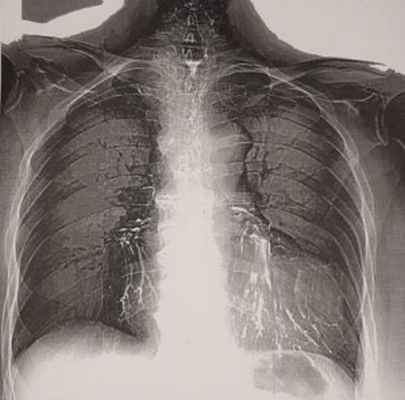

При обследовании через 3 года после операции самочувствие хорошее, физическое развитие соответствует возрасту. Одышки нет, занимается спортивной гимнастикой. Деформации грудной клетки и сколиоза, наблюдавшихся перед операцией, нет. При исследовании функции легких вентиляционная способность легких нормализовалась (жизненная емкость легких 102%, объем форсированного выдоха за 1-ю секунду 105%). Обострений туберкулеза за 3 года не было, в мокроте при всех исследованиях МБТ не обнаружены. При обзорной рентгенографии (рис. 5) Рис. 5. Обзорная рентгенограмма органов грудной клетки больной Г. через 3 года после ВАТС-плеврэктомии с декортикацией левого легкого по поводу хронической туберкулезной эмпиемы плевры. Легкие хорошо пневматизированы, признаков обострения туберкулеза нет. легкие хорошо пневматизированы, признаков обострения туберкулеза нет.